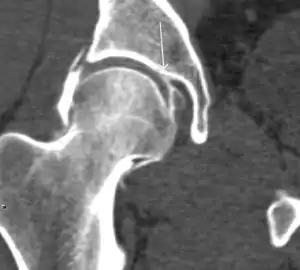

Figure 7:

Axial CT image of pigmented villonodular synovitis eroding the posterior cortex of the femoral neck.[1]